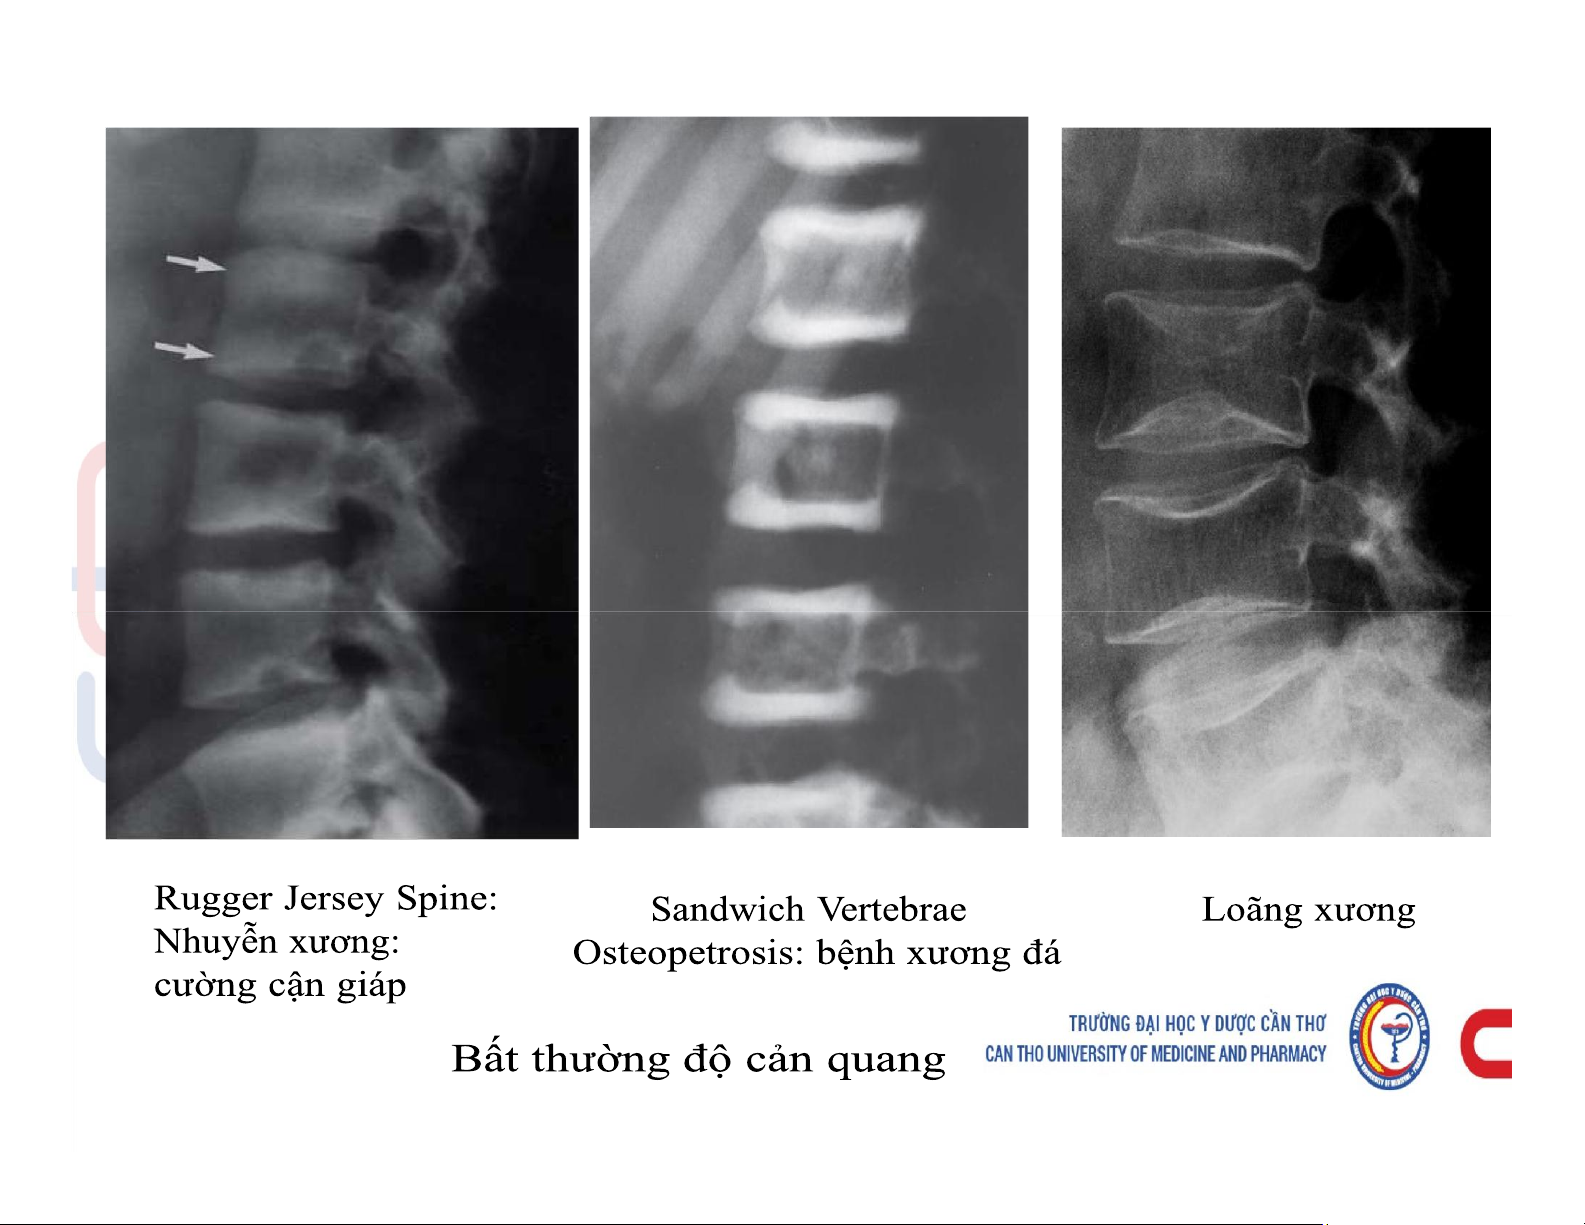

Mô tả và chú thích được các cấu trúc giải phẫu x quang xương khớp. Mô tả các dấu hiệu cơ bản trên phim x quang xương khớp. Phân tích được hình ảnh x quang bệnh lý của một số nhóm bệnh lý xương khớp. Các dấu hiệu cơ bản của phim. Tài liệu giúp bạn tham khảo, ôn tập và đạt kết quả cao. Mời đọc đón xem!